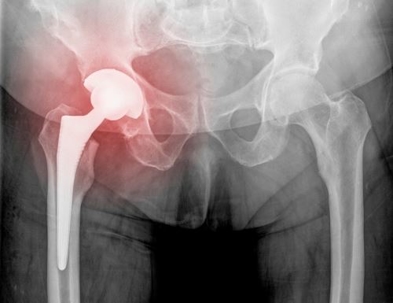

Injured Hip